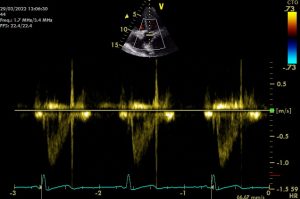

Cardiology, Oncology, Genomics